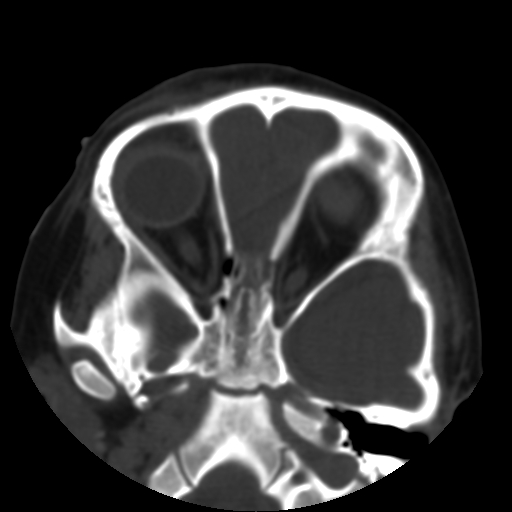

以下是引用深泽交通医院在2009-10-16 8:25:00的发言:[br]右眼环出血伴异物

以下是引用卜一在2009-10-16 15:01:00的发言:[br]右眼球挫裂伤伴异物!

以下是引用拾荒者在2009-10-17 18:38:00的发言:[br]鼻面部皮下积气,右侧睑缘及眼球壁高密度异物影,左侧眼球壁晶状体内侧缘处是圆形低密度影。低密度异物?应提请眼科医生注意。